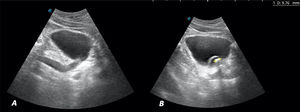

Ante el cuadro sugestivo de cólico renoureteral derecho, se decide realizar ecografía a pie de cama en consulta con los siguientes hallazgos: riñón derecho con dilatación de la vía excretora sugerente de hidronefrosis grado II/IV (figs. 1A y B). Vejiga bien replecionada con imagen anecoica tubular en el corte longitudinal que corresponde al uréter distal dilatado (fig. 2A). En el interior de la vejiga se observa imagen anecoica con borde hiperecoico bien definido que sugiere ureterocele y en su interior, una imagen hiperecoica con sombra acústica posterior de 9,76mm compatible con litiasis (fig. 2B). Riñón izquierdo (fig. 1C), hígado, vesícula y vía biliar intra y extrahepática, bazo, zona pancreática y próstata sin alteraciones.

A) Corte longitudinal. Imagen anecoica a la entrada de la vejiga, que corresponde al uréter dilatado. B) Corte longitudinal. Vejiga bien replecionada con imagen anecoica, con borde hiperecoico bien definido (imagen quística) que sugiere ureterocele. En su interior imagen hiperecoica con sombra acústica posterior de 9,76mm compatible con litiasis.

La prueba diagnóstica de elección es la ecografía, donde podrá detectarse una imagen en la pared posterior de la vejiga delimitada por una línea hiperecogénica bien definida, redondeada, de pared fina, que cambia de tamaño durante la exploración en tiempo real, sin doppler en su interior. En ocasiones se puede visualizar el uréter dilatado en la zona posterior a la vejiga2,5, como el descrito en este caso. Los uréteres son estructuras de calibre muy estrecho no visibles en ecografía de forma habitual6, salvo en situaciones patológicas donde sufran gran dilatación, como se muestra en la figura 2A. La ecografía permite, además, valorar complicaciones derivadas del ureterocele, como la dilatación del tracto urinario (reflejo ureterovesical o hidronefrosis), permitiendo establecer el grado y gravedad de la afectación renal2,5. El estudio se puede completar con otras técnicas como cistografía, urografía intravenosa, gammagrafía renal, cistoscopia y tomografía axial computarizada (TAC), según cada caso4,5.